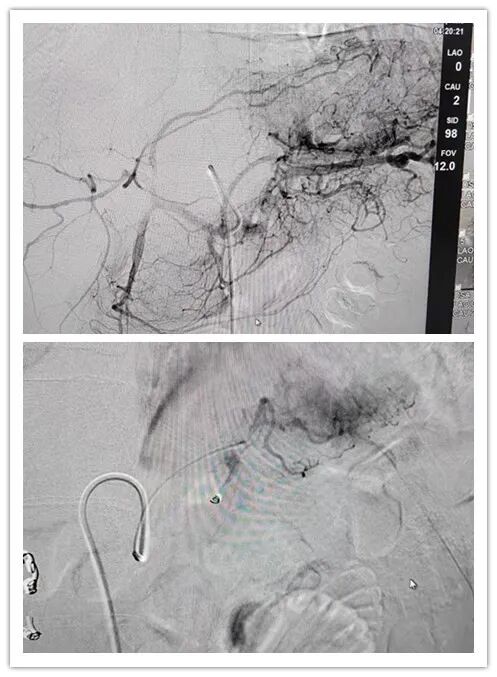

面对这样的情况,时间就是生命!修文百信医院会诊专家组立即制定

出完整的治疗方案:急诊行介入止血治疗。

经过整晚的不懈努力,抗争在死亡的边缘,该患者的血止住了!!患者生

命体征也逐渐平稳了下来,手术完美结束!

这就是介入治疗的魅力!不但挽救了一条鲜活的生命,对患者还没有

任何创伤,就是一个“小小的针眼”经过几天恢复也不会留下任何痕迹!

图片来源:介入肿瘤科